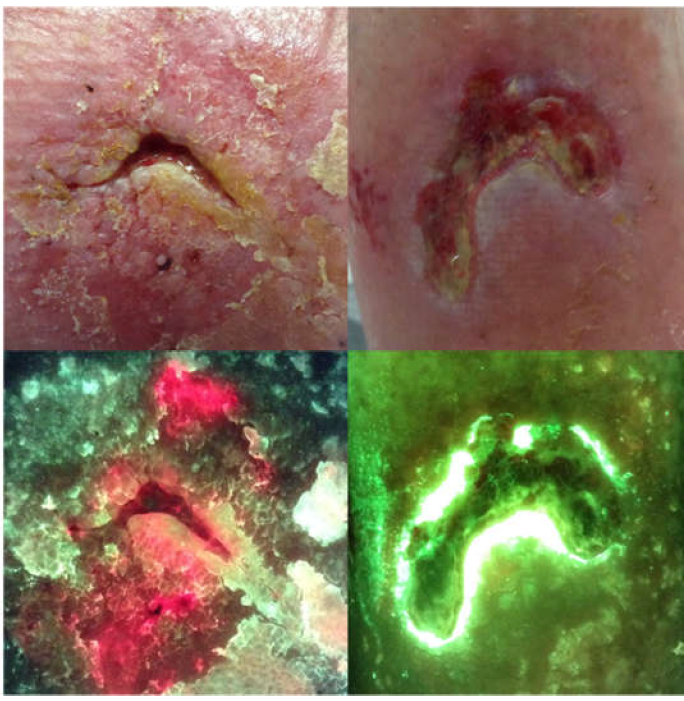

The “C-Swab” test: a technique for identifying bacteria in sinus tracts or tunneled wounds utilizing a cotton swab and bacterial fluorescence imaging

Andersen C. and McLeod K. Wounds 2025